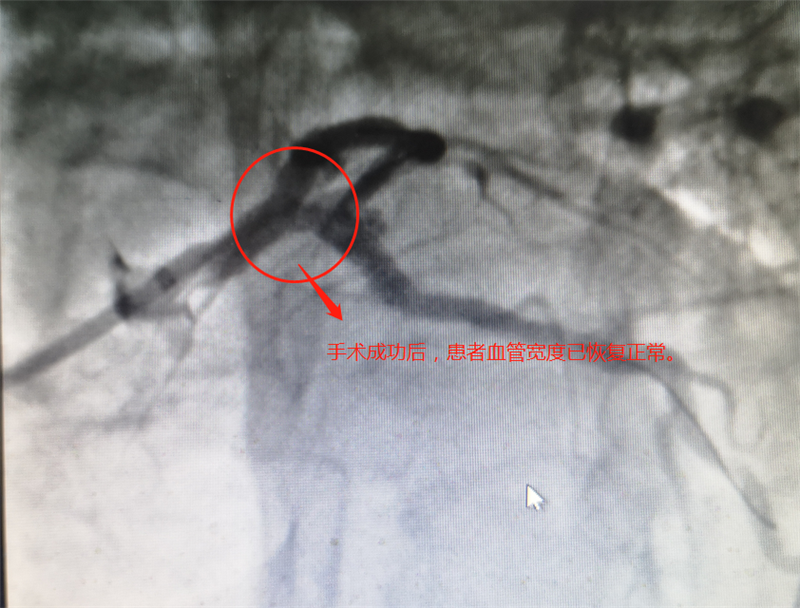

术中的李晚泉精神高度集中,在手术团队的密切配合下,三个支架顺着导丝先后抵达回旋支开口、前降支近段以及左主干的严重狭窄病变处,支架顺利打开。在植入支架过程中,先后两次用球囊沿导丝在分叉支架网状空隙处同步高压扩张支架,在两球囊的共同作用力下,两支架与分叉部位血管完美贴合,经过冠脉血管内超声(IVUS)证实结果非常满意。最重要一步终于顺利完成!三个支架在左主干分叉处形成“T”字型,影像结果达到完美预期。全程观摩的省级专家在术后也纷纷点赞:“效果完美!”

手术由李晚泉主任主刀,历时一个多小时,手术演示顺利完成。全程观摩完手术的省级专家评价道:“技术精湛,效果完美!”